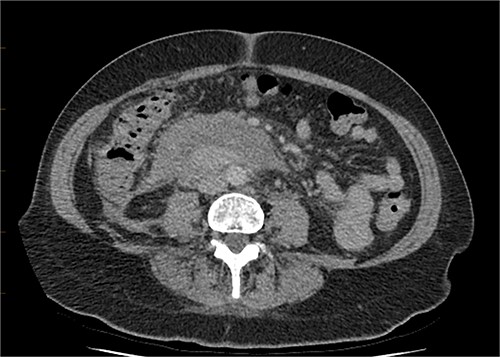

Continued observation, analgesia and fasting. On Day 2 post-admission, the patient had an urgent upper gastrointestinal endoscopy, which showed no abnormality. No ulcer, compression or inflammation was found. After the gastroscopy, the patient was started on a normal diet, which she tolerated well, and her pain had also improved. A progress CT was performed on Day 5, which showed a mild increase of the periduodenal collection with mass effect on the duodenum and evidence of mild biliary tree dilatation with the common bile duct measuring 11 mm. There was no sign of gastric outlet obstruction (Figs 7 and 8).

CT abdomen, axial view. Slight interval decrease in size of previously identified periduodenal hematoma.